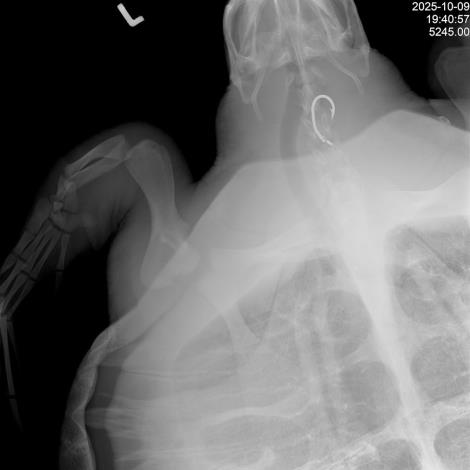

本次野放海龜是海洋保育署「海洋保育類野生動物救援組織網」於今年10月9日接獲通報,高雄蚵子寮漁港安檢所有拖網混獲到欖蠵龜一隻,並在地方政府及海巡署協助下接送至海生館治療。經檢查背甲曲線長63公分、寬67.5公分,體重30.95公斤,為亞成年個體,並於收容時進行X光檢查時發現食道內有魚鉤一枚,後續由海生館獸醫師執行內視鏡手術成功將其取出。收容照養後,評估健康及活動能力均恢復良好,今日野放使其重返海洋。

1. 圖1_海龜食道魚鉤